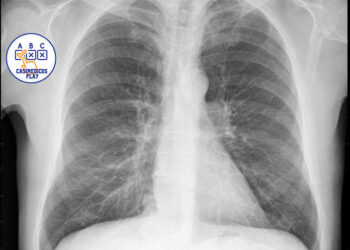

Introducción y descripción del caso

Mujer de 34 años. Es dependienta de una tienda de modas. El único antecedente clínico es artritis reumatoide desde hace 5 años, controlada con metrotrexate y sin brotes desde hace 2 años. No tiene hábitos tóxicos. Al final de una consulta rutinaria, refiere que desde hace 3 días presenta dolor abdominal bajo de tipo cólico, de intensidad leve, no relacionada con un cambio de habito intestinal, ni con trasgresión dietética, ni con alteración menstrual.

Se observa una perdida de peso leve,( 3 kg), en los últimos tres meses, aunque refiere que lleva mucho estrés en el trabajo y come mal. No presenta síndrome miccional ni fiebre ni otras sintomatologías. La exploración abdominal es anodina, se solicita hemograma y bioquímica general, test de sangre oculta en heces. Se pauta dieta y espasmolíticos, y observación domiciliaria. Al día siguiente vuelve a consultar por el dolor abdominal, aunque refiere que es más intenso, y que se va acompañado de nauseas y un vomito, y una deposición blanda con hebras de sangre. En la exploración abdominal presenta un abdomen poco depresible, dolor en fosa iliaca derecha, con Signo de blumberg positivo, por lo que se remite a Urgencias hospitalarias con diagnostico de abdomen agudo. Es valorada por el cirujano decidiéndose intervención quirúrgica, detectándose un plastron inflamatorio abscesificado a nivel de ileon distal y colon proximal, se hace resección parcial, siendo dada de alta 10 días después. Actualmente lleva 3 meses estable y sin nueva crisis.